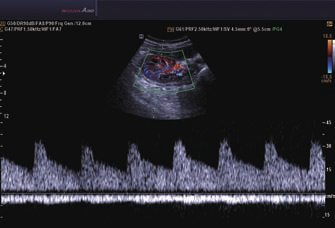

• Continuous Wave (CW)-Doppler

• Tissue Doppler Imaging (TDI; Gewebe-Doppler-Bildgebung)

• Tissue Doppler Wave (TDW; Gewebe-Doppler-Welle)

• Farb-M-Modus

• Anatomischer M-Modus

• Color Opt Flow™ bietet kraftvollere Farben und verbessert die Bildqualität.